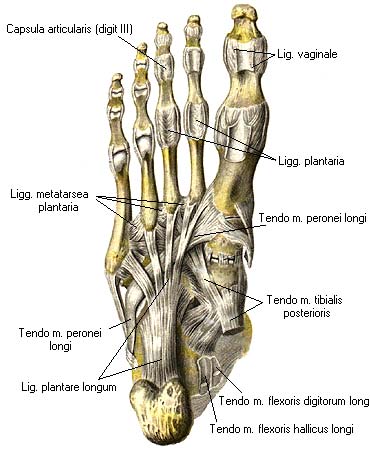

Анатомия суставов Шапарова и Лисфранка: фото и информация